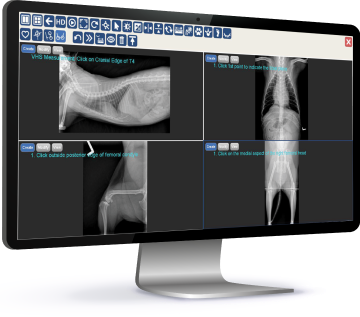

Powered by ExamVue™ Acquisition Software

DynaVue™ Duo is powered by

Specialized Tools for Veterinarians

🔹Axial Angle

🔹Clock Face

🔹Clock Face (Lat View)

🔹Clock Face (VD View)

🔹Cross Angle

🔹Liver Size

🔹Middle Angle

🔹Norberg Angle

🔹Percent Coverage

🔹Spine Label

🔹TPA

🔹Vertical Discrepancy

🔹VHS

🔹VLAS

🔹Vertebral Heart Score

🔹Norberg Hip Analysis

🔹TPLO Analysis

🔹TTA Analysis